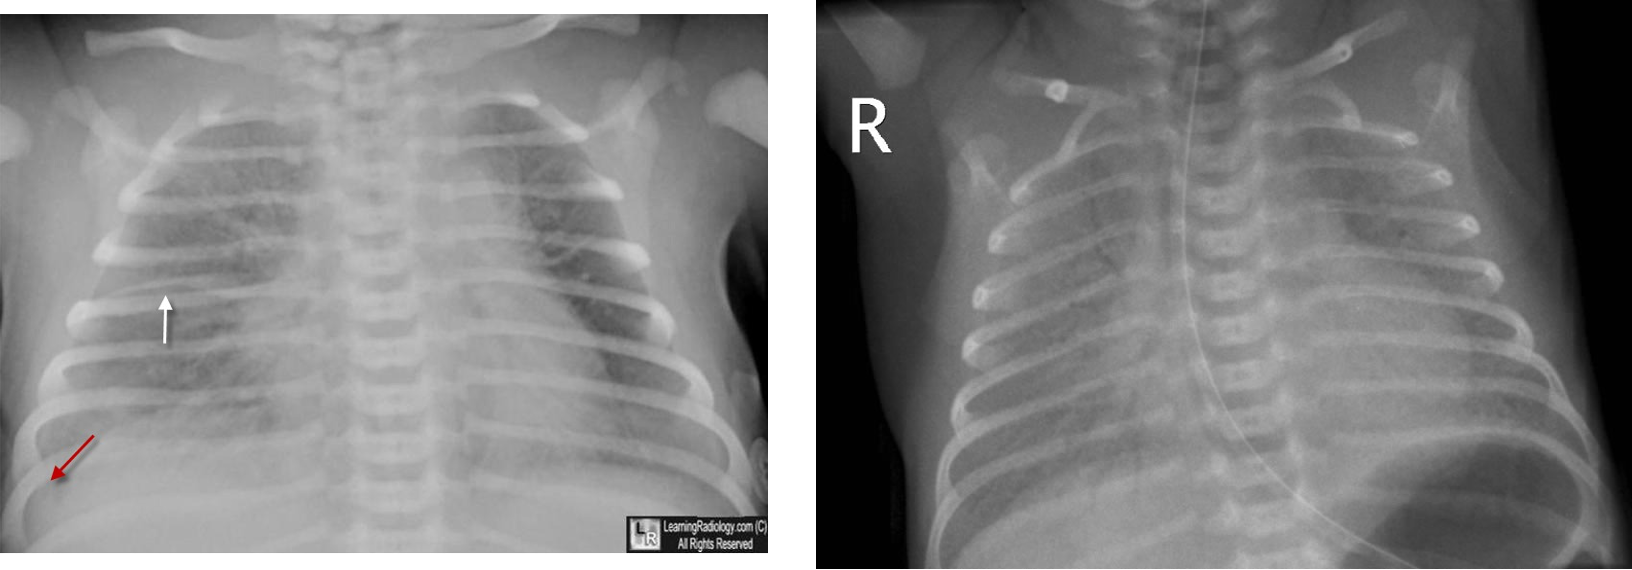

Imaging

- Small to N cardiac silhouette

- Decrease pulmonary vasculature